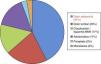

Su etiología es variable: espontánea, traumática, iatrogénica. A día de hoy la más frecuente es de origen idiopático o espontáneo (fig. 3). La clínica es poco específica, pero conjuntamente con los factores de riesgo nos ayudará ante la sospecha de dicho cuadro. Así puede cursar con: dolor abdominal y/o torácico, cuadros isquémicos a diferente niveles, y en un porcentaje nada desdeñable, el cuadro clínico es asintomático (17%)2 (fig. 4). El diagnóstico de confirmación se realiza en más de la mitad de los casos mediante angio-TAC (75%), aunque también se puede realizar a través de estudios ecográficos, angiográficos o con angio-RM5.